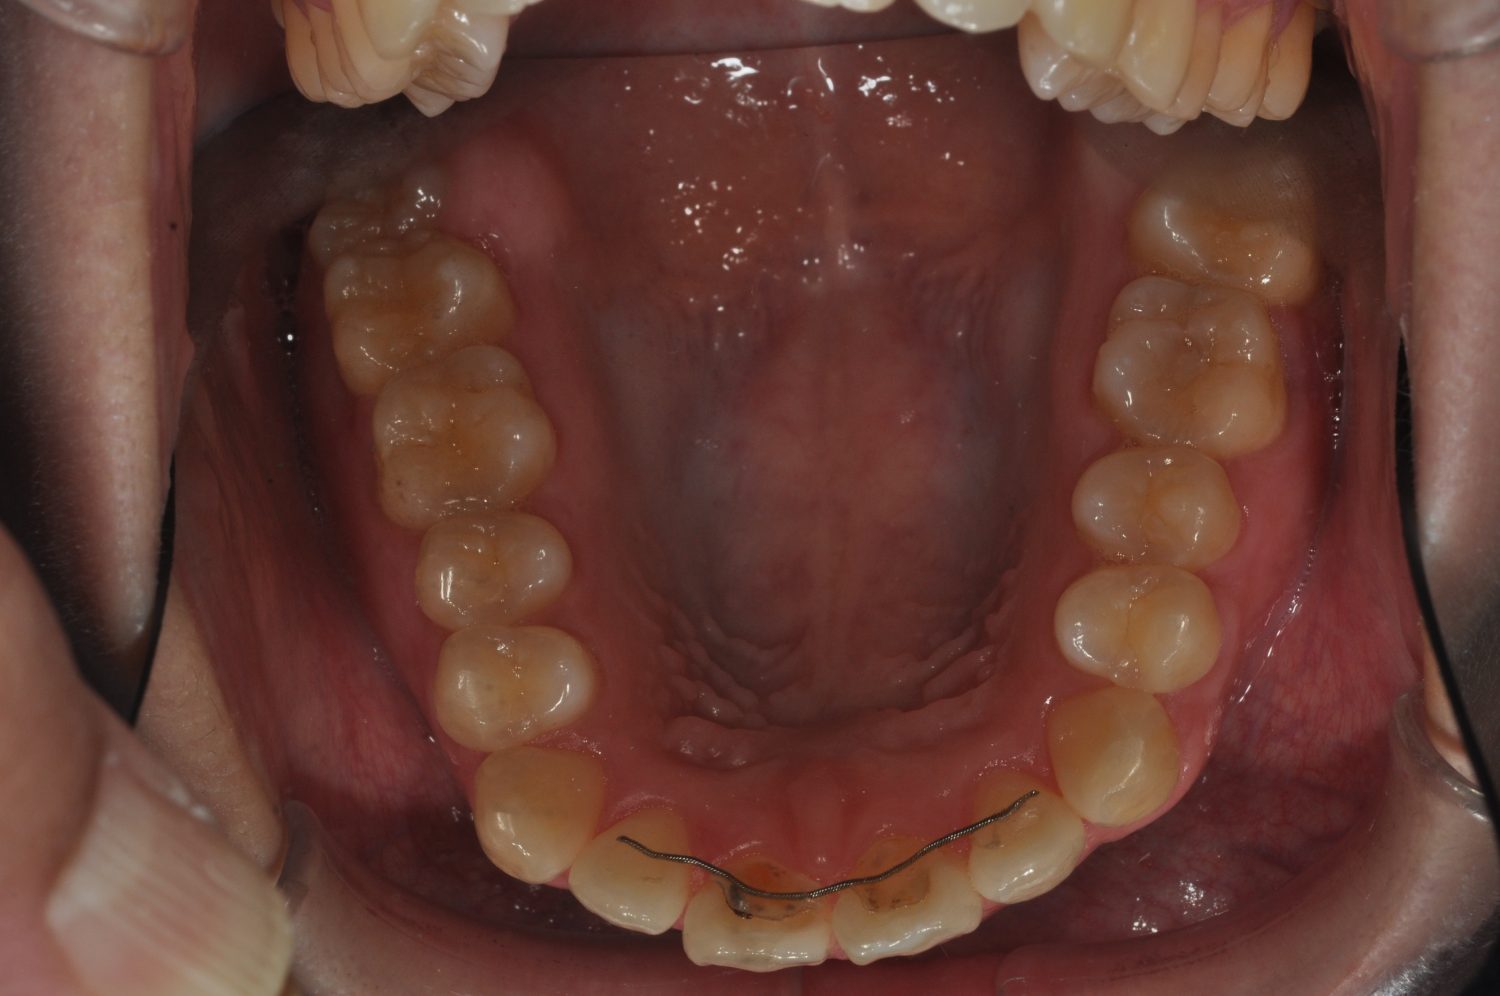

| 主訴 | 口上下顎のガチャガチャが気になる |

| 治療内容 | 歯冠幅径が大きいことから、IPRを併用した非抜歯治療 |

| 治療費 | Ⅱ期治療費:247,500円(税込) 調整料 5500円(税込)×11回 保定時:22,000円(税込) 計 330,000円(税込) |

| 治療期間 | 1年2ヶ月 |

| 治療回数 | 13回 |

| 想定されたリスク | 矯正中の清掃状況によってはむし歯や歯周病のリスクがありました。歯根吸収や歯肉退縮のリスクもありました。 |

Ⅰ期治療で前歯部反対咬合をセクショナルアーチとMPAを使用して改善した後、成長観察を行っていました。永久歯が萌出したため、Ⅱ期治療を開始することとなった。上下顎とも骨格的に問題がなかったため、非抜歯で治療を行った。